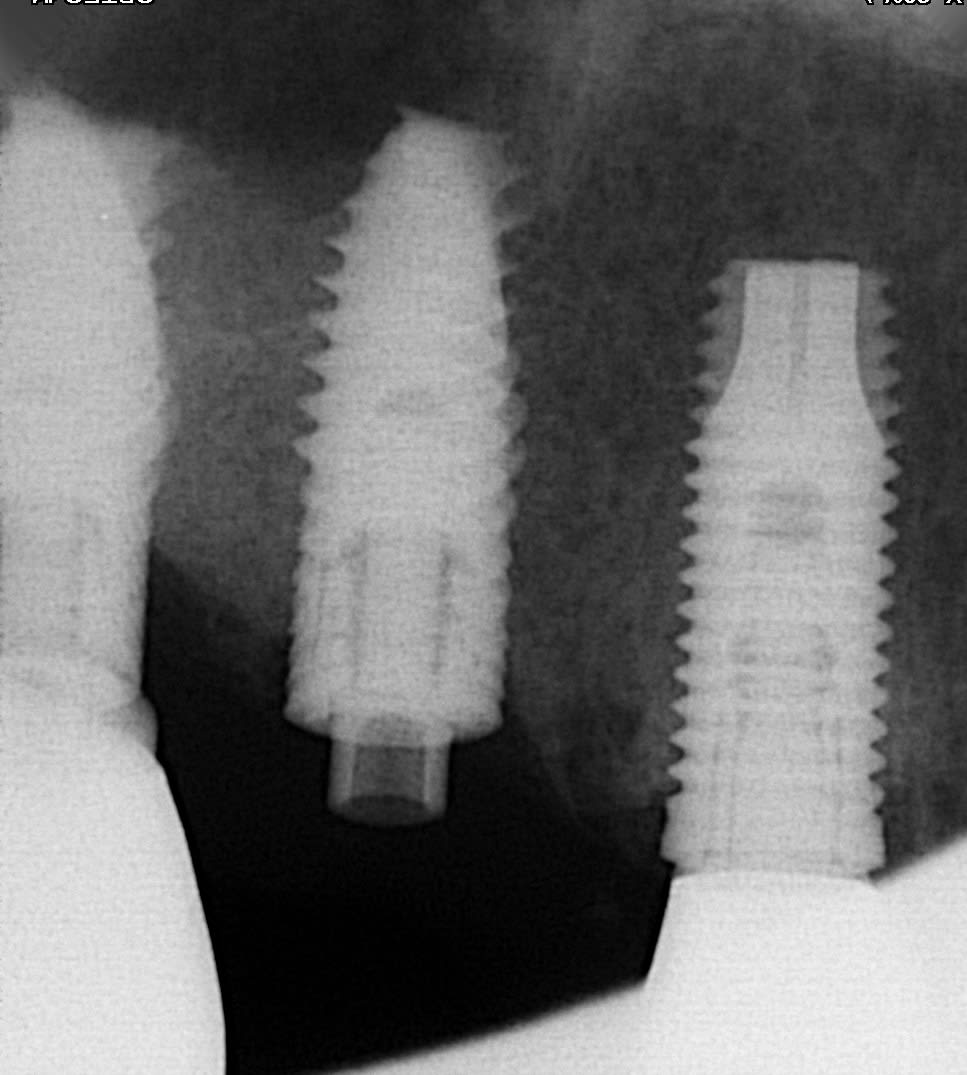

je cherche la marque de cet implant dont la partie prothétique à cassée avec la connectique interne...